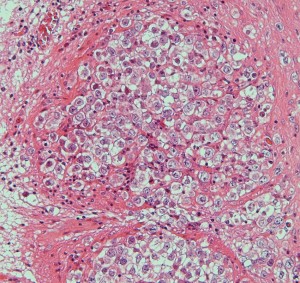

病理所見です

epidermisにhair follicle, sebaseous glandを伴うdermoid cyst 類皮のう胞の診断です。上皮に接する脳組織(これは正常脳組織ではなくて成熟奇形腫の内部にできた脳組織)の内部にgerm cell nest(矢印)が認められました(左下拡大)。mature teratomaにgerminomaが混在するmixed germ cell tumor と診断されました。